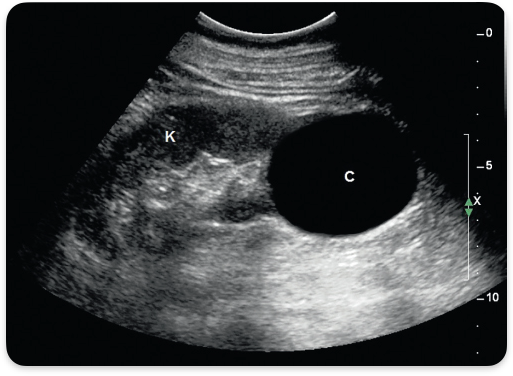

Simple renal cyst. Anechoic, smooth walls, posterior enhancement.

Complex renal cyst. septations, debris, irregular borders, papillary projections.